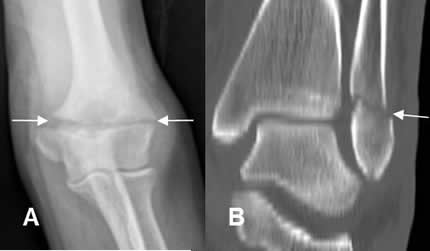

Fig 34. Fractura transversa.

A: Rx AP y B: TAC reconstrucción coronal. Fracturas transversas en el húmero distal y el maléolo externo.